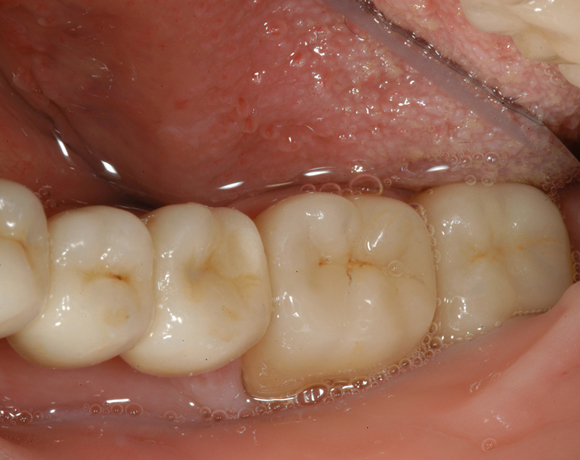

6 Implantate und viele Kronen und Brücken

Mit dem zweiteiligen vollkeramischen Implantat lassen sich auch große Lücken überbrücken.

Ein Projekt aus dem Jahr 2011

Im vorliegenden Patientenfall waren die Zähne 11 – 26 mit einer provisorischen Brücke versorgt, der Patient konnte damit aber nicht essen. Auch im Unterkiefer waren die vorhandenen Kronen und Brücken insuffizient. Es wurde eine komplette Neuversorgung für Ober- wie Unterkiefer geplant.